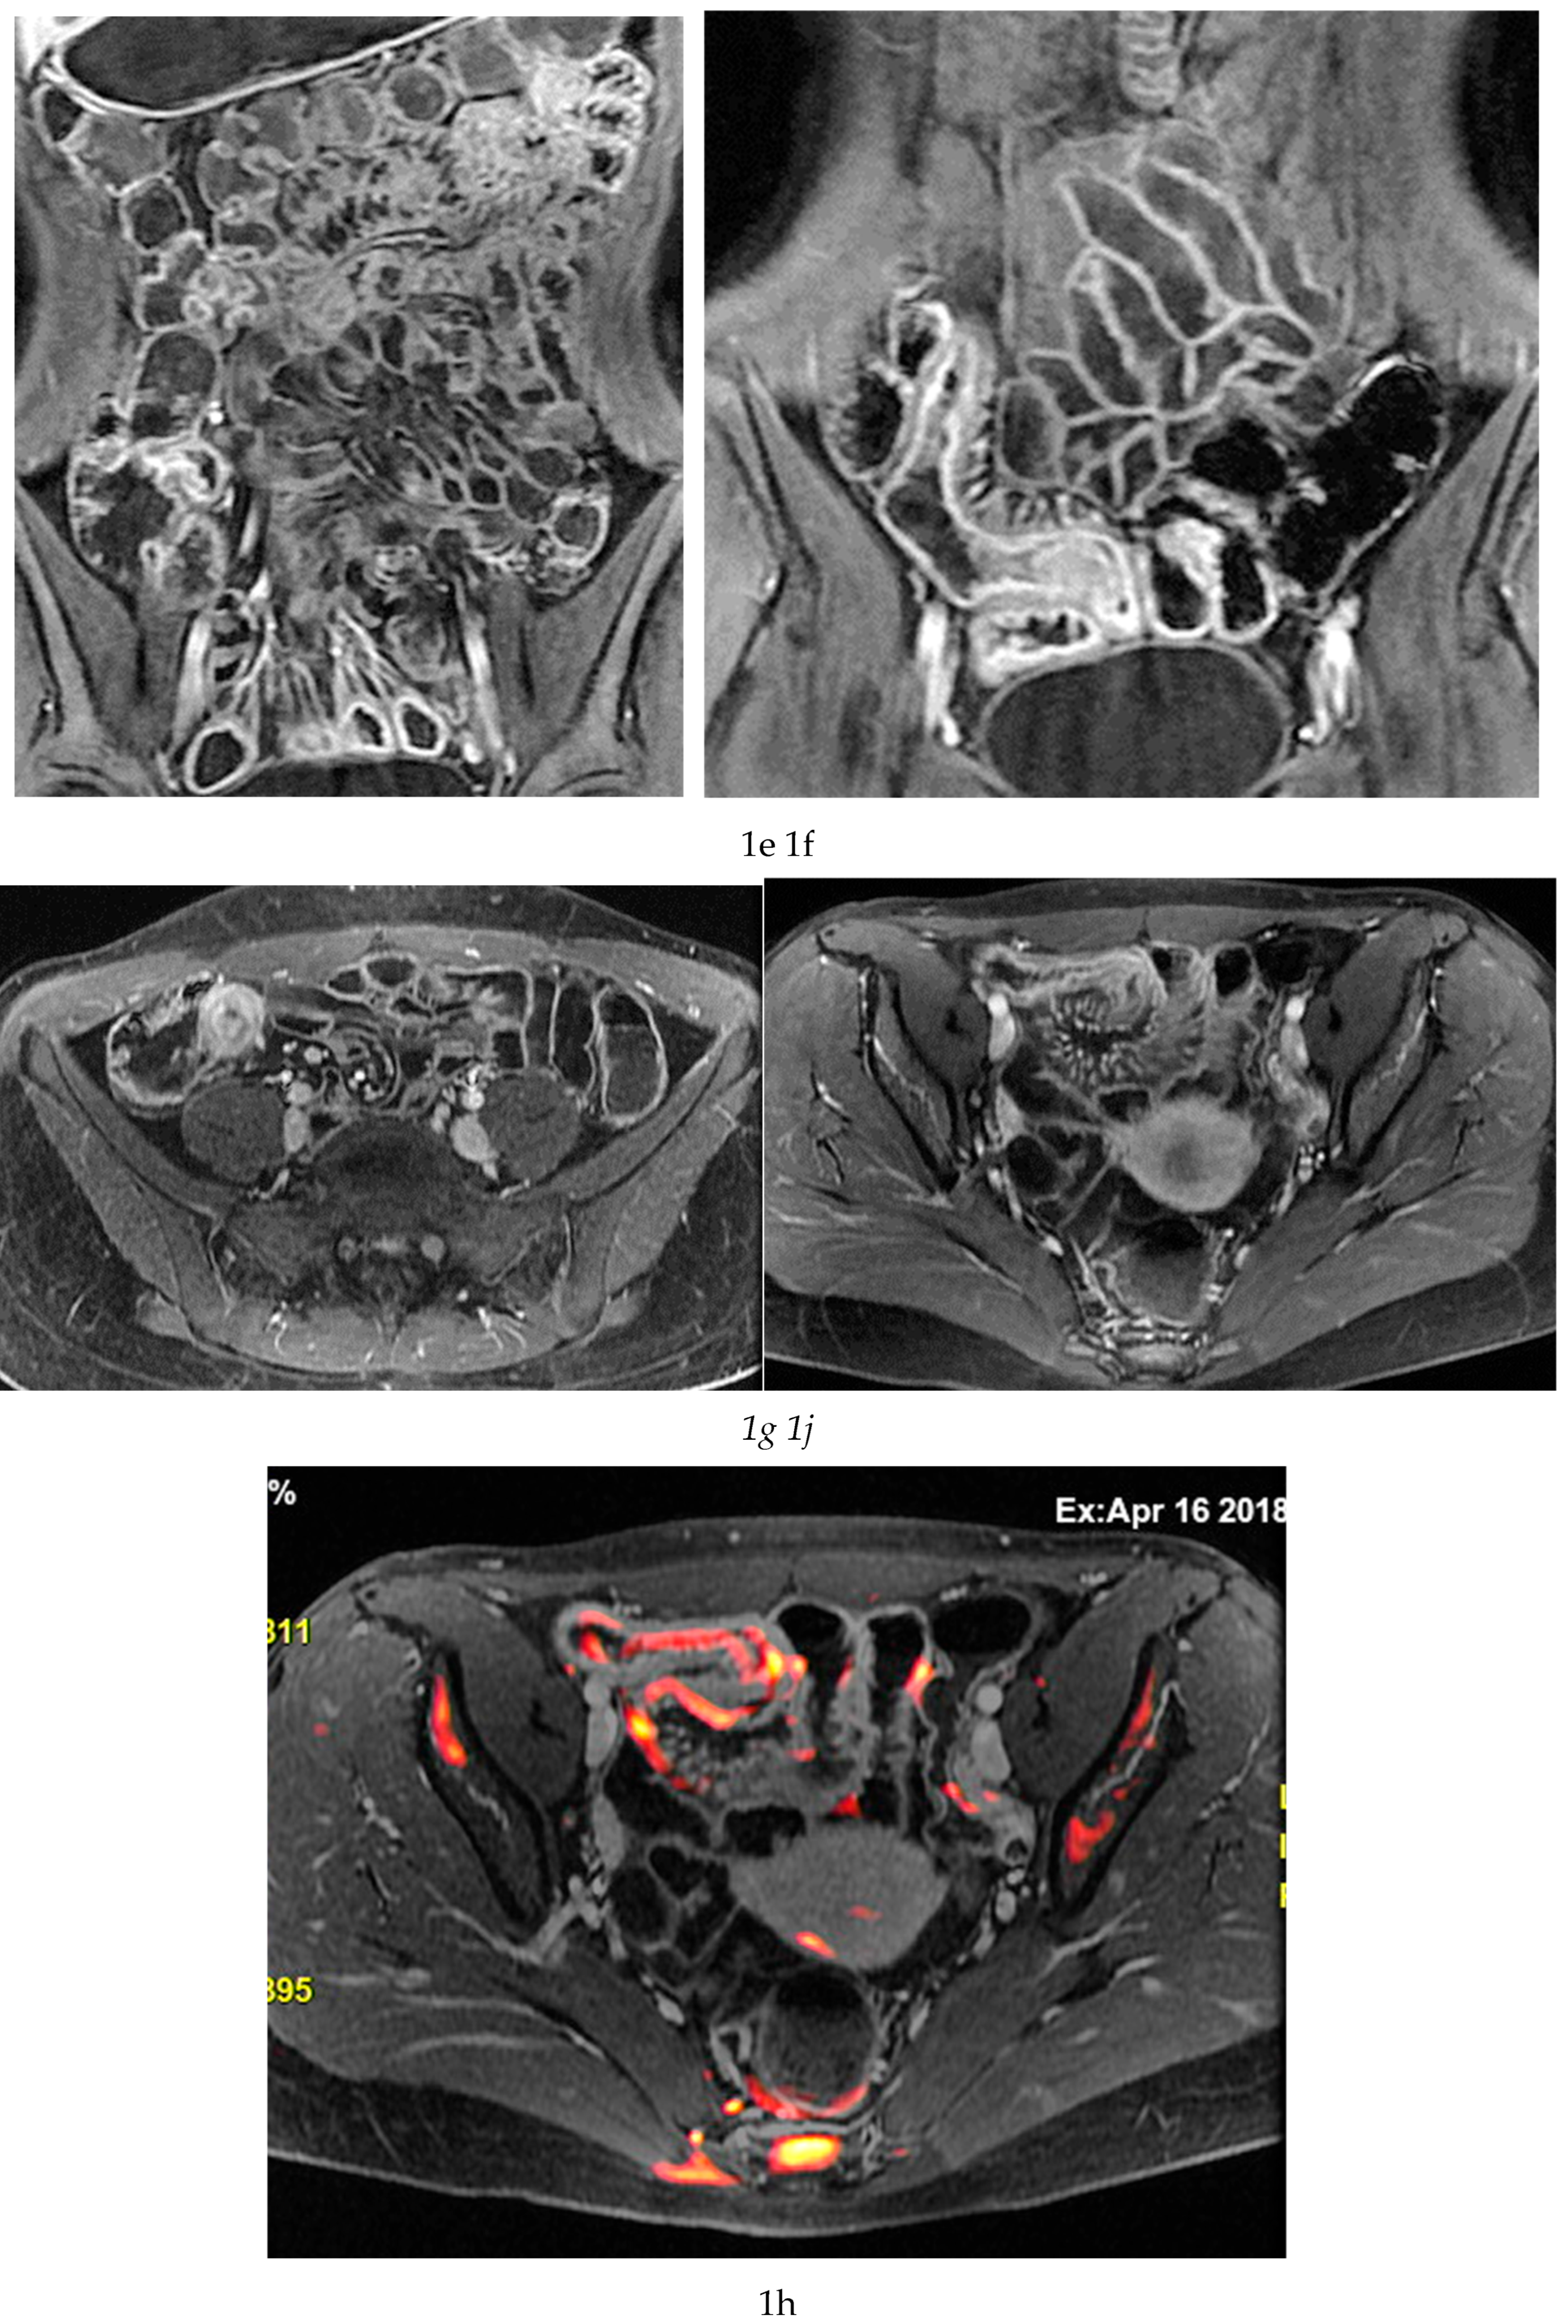

Multiparametric MRE protocols therefore combine a series of complementary sequences, each providing distinct and synergistic diagnostic information. T2-weighted sequences (

Figure 1a-c) are fundamental for a comprehensive morphological assessment of Crohn’s disease on both axial and coronal planes. They allow accurate definition of disease location, longitudinal extent, and severity, including evaluation of bowel wall thickening, luminal narrowing, and the presence of penetrating complications such as fistulas and abscesses at any level of the small and large bowel. These sequences are also essential for assessing extraintestinal manifestations of disease, including inflammatory changes of the surrounding mesenteric fat. Beyond structural assessment, T2-weighted imaging plays a pivotal role in the detection of inflammatory activity through the identification of mural and mesenteric oedema. Fat-suppressed T2-weighted sequences, in particular, enhance the conspicuity of high-signal oedematous tissue and currently represent the only imaging technique capable of directly demonstrating oedema at the level of the intestinal wall, mesenteric lymph nodes, and mesentery. Oedema is a hallmark of active inflammation and reflects increased vascular permeability and interstitial fluid accumulation [

Figure 1d-g), which reflect bowel wall vascularity and the degree of inflammatory activity. These sequences are essential for evaluating not only the affected bowel segments, but also associated inflammatory changes in the mesentery and regional lymph nodes.

In addition, analysis of enhancement behaviour over time is clinically informative: early, intense enhancement is typically associated with active inflammation, whereas delayed and more progressive enhancement may provide indirect information on the presence of fibrotic components within the bowel wall. This temporal evaluation of contrast enhancement therefore contributes to distinguishing predominantly inflammatory disease from mixed or fibrostenotic phenotypes, supporting more tailored therapeutic decision-making. [

MRE is equally valuable in the detection of penetrating complications, an area where its sensitivity rivals or surpasses that of CT [

11]. The modality excels in identifying entero-enteric and entero-colonic fistulas, subtle sinus tracts, intramural or mesenteric abscesses, and inflammatory phlegmons. These complications carry significant prognostic weight, often predicting a more aggressive disease course and influencing therapeutic strategies. Because MRE can evaluate both mural and extramural structures comprehensively, it provides a more complete assessment of disease behaviour than endoscopy alone [

9] (

Figure 1 and

Figure 2).